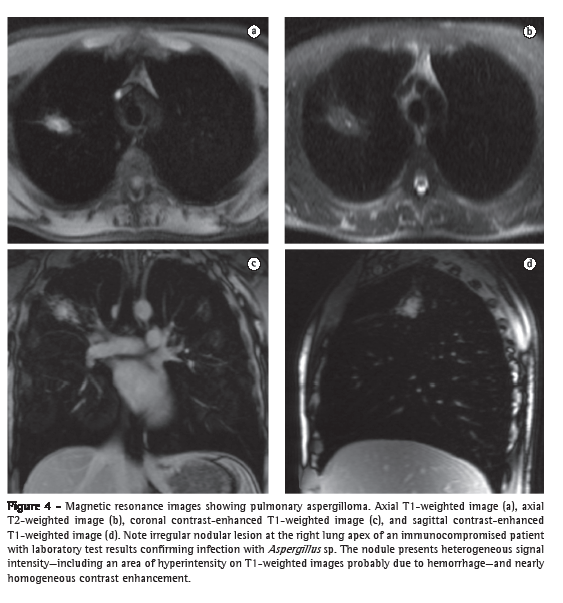

In the characterization of central lung cancer with obstructive pneumonia or atelectasis, MRI is useful and differentiates a tumor mass from secondary changes, which present increased signal intensity on T2-weighted images and a more homogeneous appearance (due to the accumulation of secretions and fluid), as well as an enhancement pattern that is different from that of the neoplastic lesion.(34) In invasive pulmonary aspergillosis, MRI is more specific than CT in characterizing consolidations associated with hemorrhagic infarction secondary to vascular invasion (Figure 4).

Hemorrhages appear as areas (commonly peripheral) of hyperintensity on T1-weighted images, whereas contrast-enhanced MRI allows the identification of areas of active inflammation, central necrosis, and abscess formation. The peculiar characteristics of the signal indicating hemoglobin degradation products and of that indicating fat degradation products also allow MRI to aid in the diagnosis of hemorrhagic pulmonary infarction, alveolar hemorrhage (as occurs in the Goodpasture's syndrome), and lipoid pneumonia associated with mineral oil aspiration.(35)